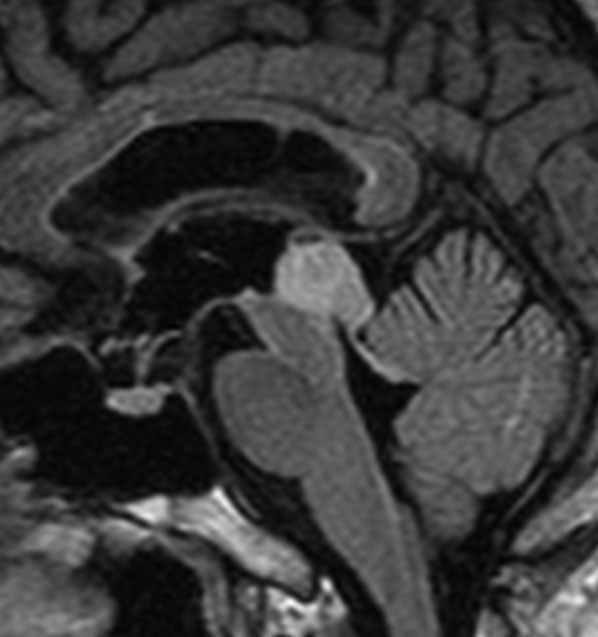

左はT2強調画像,右はFLAIR画像です。中脳視蓋 tectum の中でも上丘が腫瘍化していることが解りますし,松果体は正常の大きさで腫瘍の上に乗っていますから,松果体腫瘍ではないことが解ります。上髄帆にも浸潤しています。